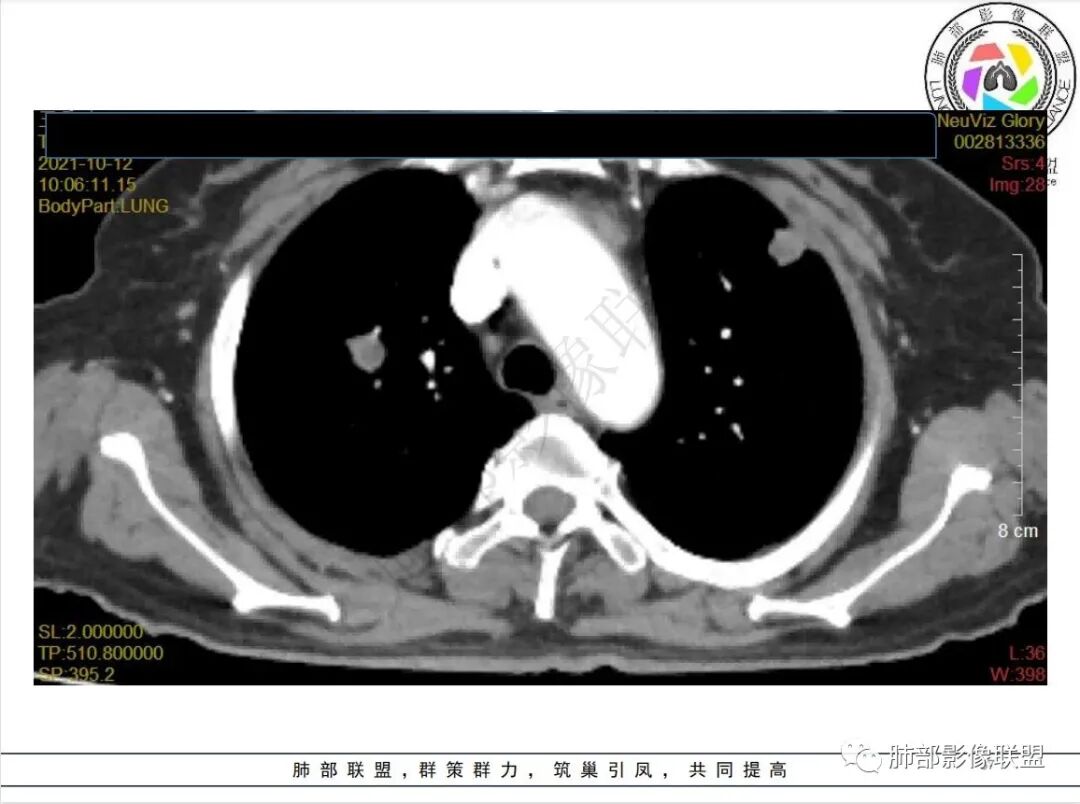

白血病化疗后,出现多发结节,边缘可见晕征,病灶内可见多发坏死,右肺中叶肺动脉可见充盈缺损,右肺中叶可见融冰征,考虑毛霉菌,右肺中叶肺动脉栓塞伴右肺中叶肺梗死。

4.白血病化疗后,CT上出现多发结节,边缘可见晕征,病灶内可见多发坏死,右肺中叶肺动脉可见充盈缺损,右肺中叶可见融冰征,右肺中叶肺动脉侵犯栓塞伴右肺中叶肺梗死,可符合真菌感染。

6.肺曲霉病典型的CT表现是结节周围有磨玻璃样的晕征表现,或胸膜为宽基底的楔形实变。晕征表现为曲菌感染的肺结节伴梗死和凝固性坏死,周围有肺泡出血。最终可出现空泡征象,并可观察到中央坏死组织与周围肺实质分离形成空气新月征。

晕征已被认为是侵袭性曲菌病的早期征象之一。